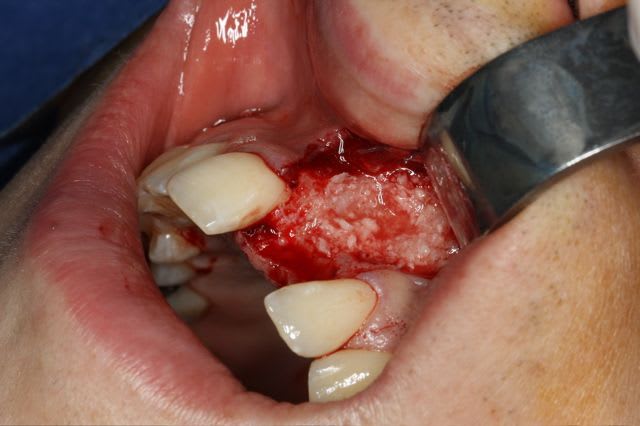

très classiquement:

greffe onaly,

pour la greffe: un lit de copeaux généreux et un bloc corticale par dessus et des copeaux pour boucher les espaces. Pas de membrane par dessus, seulement le périoste.